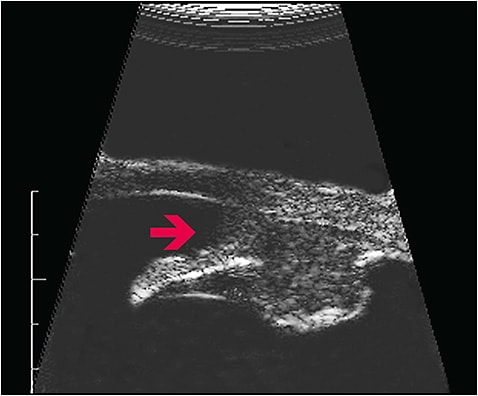

Other common angle infiltration suspects include iris tumors and ciliary body tumors (Figures 1 and 2).1 Tumors in the angle can directly damage the trabecular meshwork and Schlemm’s canal, impairing aqueous outflow.1 Tumor-related angle closure is often due to a ciliary body or ring melanoma, where the tumor arises from the ciliary body and pushes the iris and/or lens forward.11 These glaucomas are more difficult to diagnose because the tumor is hidden behind the iris. Uveal melanomas, retinoblastomas, adenocarcinomas, and medulloepithelioma can force anterior displacement of the lens–iris diaphragm.12,13 Tumor-driven angle closure may be asymmetrically located in the angle, may not respond to laser iridotomy, and should be visualized by ultrasound biomicroscopy (Figure 3).1